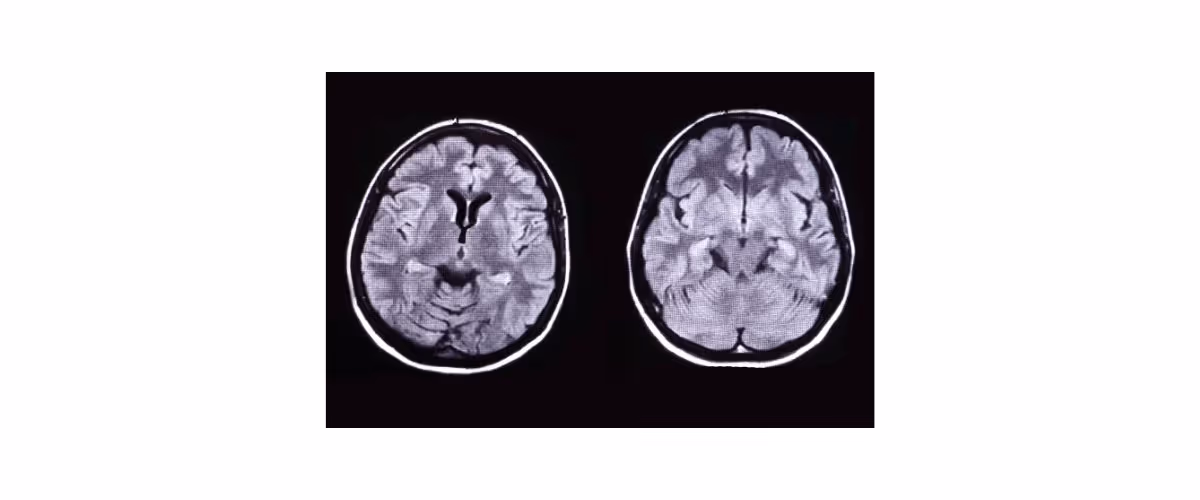

3. สมองและไขสันหลังอักเสบหลังการติดเชื้อ (Acute disseminated encephalomyelitis and myelitis, ADEM)

มักเกิดตามหลังการติดเชื้อ ส่วนใหญ่ประมาณ 1-2 สัปดาห์ ผู้ป่วยจะมีอาการได้หลากหลาย เช่น กลืนลำบาก เสียงเปลี่ยน ระดับการรู้สติลดลง หรือชัก เป็นต้น ซึ่งอาการเหล่านี้จำเป็นต้องหาสาเหตุเพื่อแยกโรค เนื่องจากภาวะนี้เกิดจากปฏิกิริยาภูมิคุ้มกันของร่างกายในระดับรุนแรงหลังจากได้รับเชื้อ ทำให้มีรอยโรคในเนื้อสมองและไขสันหลังหลายตำแหน่ง แต่ไม่พบเชื้อในน้ำไขสันหลัง การรักษาจำเป็นต้องหายากดภูมิคุ้มกัน หรือบำบัดด้วยอิมมูโนโกลบูลิน

(รูปภาพมาจาก Ellul MA, Benjamin L, Singh B, Lant S, Michael BD, Easton A, et al. Neurological associations of COVID-19. The Lancet Neurology. 2020 Sep;19(9):767-83.)